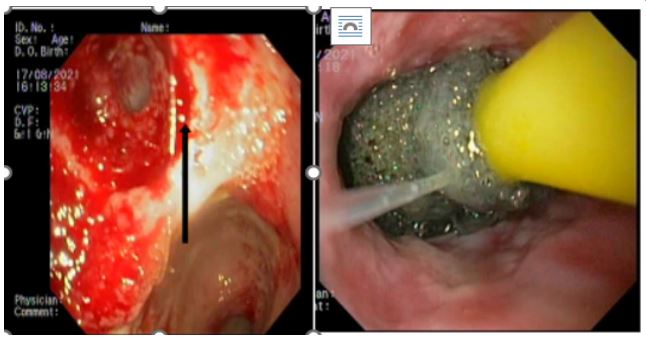

A 59-year-old man has complained of pus and mucus discharge from the anal region, as well as intermittent fever episodes, for the past two years. Three years ago, he developed symptoms of per rectal bleeding and was diagnosed with Carcinoma rectum, for which he received three cycles of neoadjuvant radiotherapy followed by laparoscopic anterior resection with a defuncting descending colostomy. He was discharged on post-operative day 8, with no issues reported. Adjuvant Chemotherapy was administered in 13 cycles. After 6 months of surgery, a CT abdomen was performed, which showed post-op changes in the pelvis with Pelvic peritoneal fat stranding and widening of the presacral space. He was having repeated episodes of fever with chills and pus discharge per anus that were resolved with IV antibiotics. After 6 months, an MRI of the pelvis revealed a significant collection of size 9.1 x 5.2 x 8.8 cm with air loculi at the presacral area-most likely a controlled leak (Figure 2). The conservative approach was continued for another six weeks, during which an intermittent fever with mucus and pus discharge from the anal region persisted. A colonoscopy was performed, which showed the cavity and confirmed the findings (Figure 4). Endovac sponges were sutured to RT and placed directly into the cavity with the help of a colonoscope after debriding and irrigating the cavity. After applying post-E-VAC therapy, the patient improved and had no fever after 48 hours. The procedure was repeated on an OPD basis four more times, with the endovac in place for five days each. At each session of endoscopy, there was a reduction in the size of the sponge used and considerable improvement in terms of the size of the cavity and the amount of slough (Figure 5). The cavity completely healed 10 weeks after E-VAC therapy, and the patient has been asymptomatic for the past 4 months. A CT scan showed complete resolution of the leak.

Figure 4: Colonoscopy showing post operative leak after anterior resection of ca rectum and placement of EVAC.

Figure 5: Healing of rectal cavity after E- Vac.